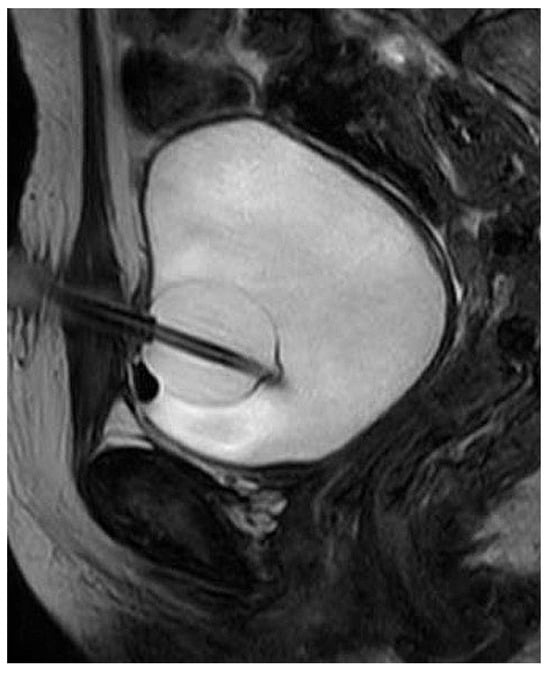

We retrospectively and prospectively collected data on girls and women referred to our center for PFUI repair between 1995 and 2021. A detailed history was obtained, and patients were examined in the outpatient clinic. We obtained an ultrasound of the abdomen. Additionally, we annotated the position of suprapubic catheter and any previous scars on the abdomen, and we performed a local examination of the vulva. The female urethra is about 4 cm in length, and even smaller in young women and girls. Retrograde urethrogram and voiding cystourethrogram were considered critical for assessment of the urethral injury, and all patients received pelvic MRI, in which the bladder and urethra were filled with saline solution and jelly to enhance the lumen and the level of the urethral distraction (Figure 1 and Figure 2) [12].

Figure 1.

MRI in female patient with pelvic fracture urethral injury.